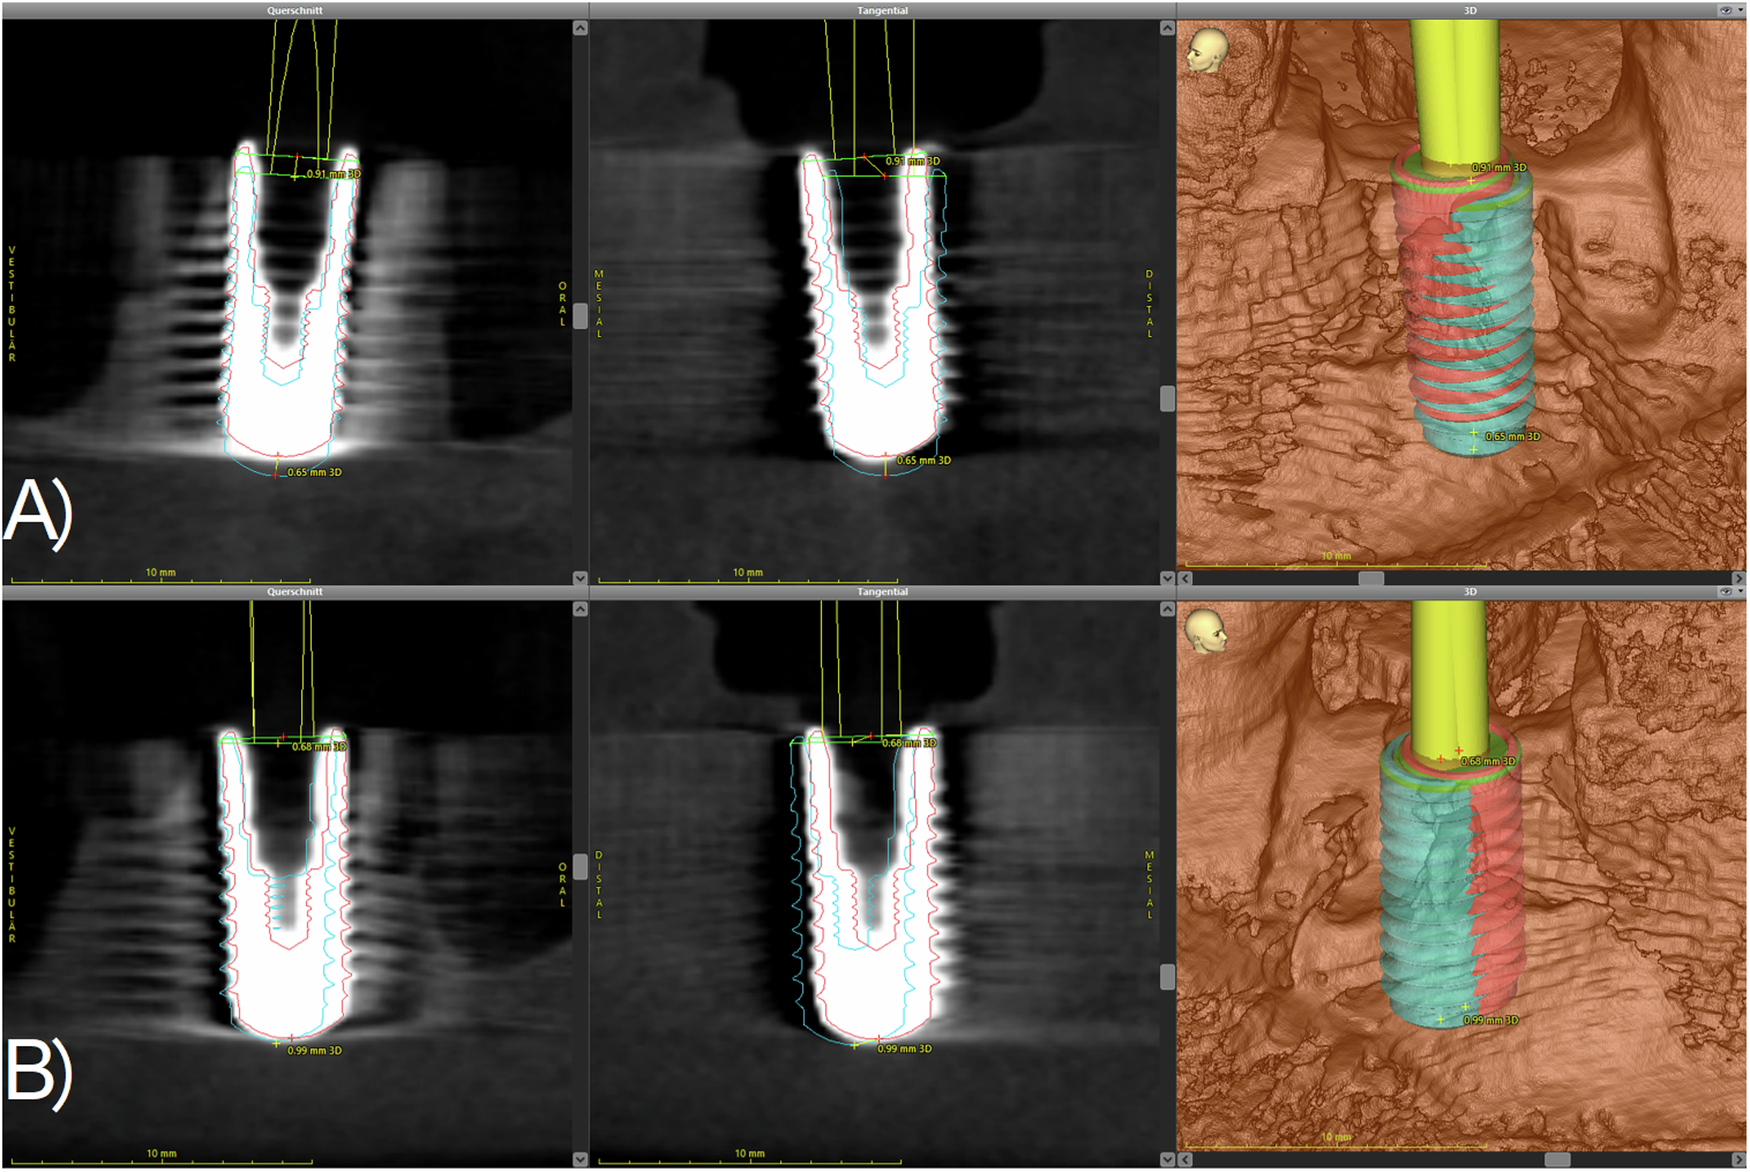

Fig. 2: Scheme of the superimposition of the planned (blue) and the actually achieved (red) implant position.

A The implant in region 36 (upper) shows a slightly mesial deviation from the planned position. Furthermore, the implant is placed a bit too crestal compared to the planned position. B The implant in region 46 (lower) shows a slight oral and mesial mismatch compared to the planned position.